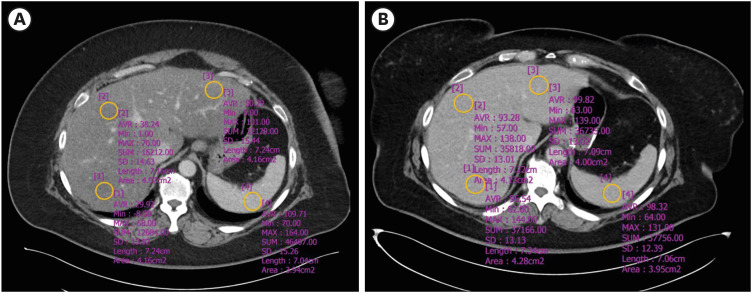

Purpose: Non-alcoholic fatty liver disease (NAFLD) is becoming increasingly common, especially among obese individuals. This study evaluated the liver/spleen Hounsfield unit (HU) ratio (L/S ratio) as an indicator of steatosis and related metabolic diseases using contrast-enhanced computed tomography (CT).

Materials and methods: A retrospective analysis was conducted on 34 patients who underwent bariatric surgery at Eunpyeong St. Mary's Hospital between March 2019 and July 2023. All patients underwent CT scans before and 6 months after surgery. The L/S ratio was calculated by dividing the average value of 3 HU of the liver by that of the spleen. The ratio correlated with pre- and post-surgery weight changes, comorbidities, and laboratory findings.